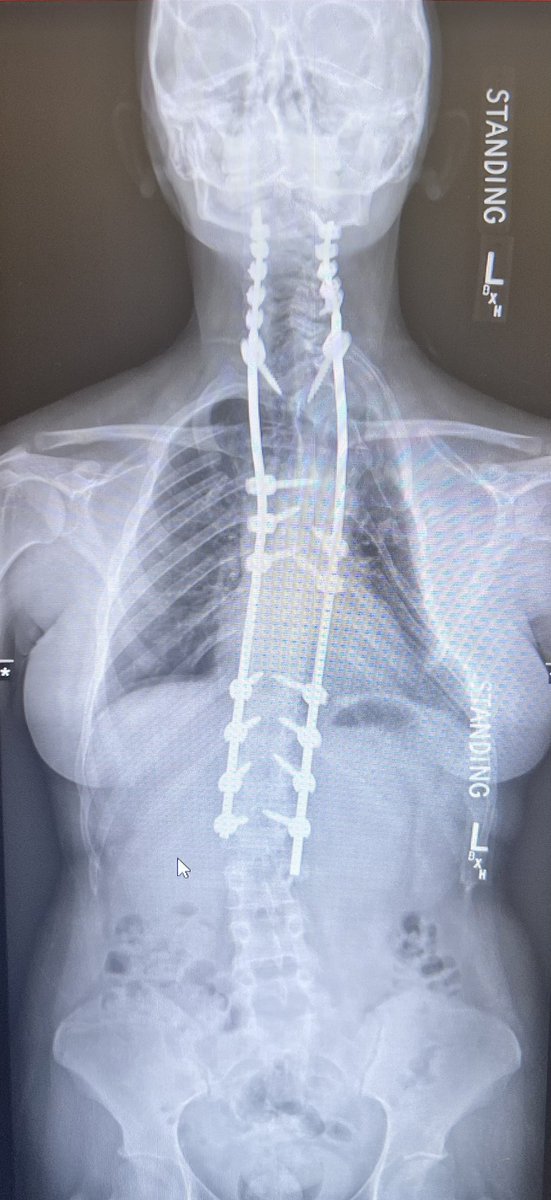

Pre-and post-op awake MIS fusion to correct this patient scoliosis. @mayoclinic our associate surgeon @RodNavarroMD work hand in hand to learn the latest approach, enabling technology and freehand. Accepting applications for 2024-2025. @DoctorQMd @oakinduroMD @wchrisfox

Very satisfying case not only because of the deformity correction we achieved but more importantly because of the impact this surgery had on the patient’s life. @MayoClinicNeuro patient specific 3D printing for planning. https://t.co/Nz6Yehvu7Y! For new appointments #scoliosis